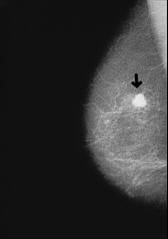

Der Organismus der Blutgruppe AB ist für Brustkrebs genau so anfällig wie die Blutgruppe A (4 Strategien, S.187).

[1] Brustkrebs, Röntgenfoto: http://www.prof-obwegeser.at/brustkrebs.htm